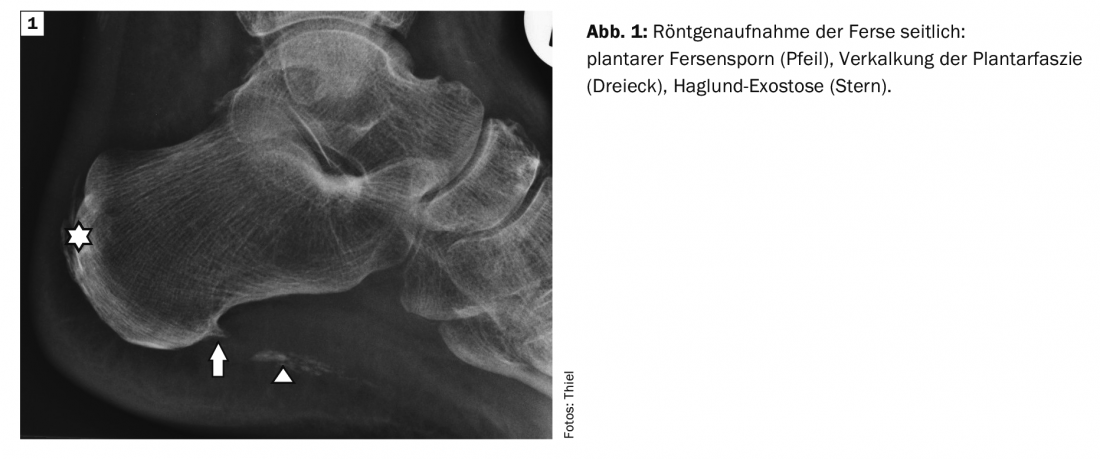

L’exemple 1 montre une radiographie latérale de la cheville gauche chez une patiente de 70 ans présentant des symptômes de douleurs plantaires bilatérales à l’effort et après l’effort, une épine calcanéenne plantaire et dorsale ainsi qu’une calcification étendue sur le trajet du fascia plantaire. L’image du talon droit, qui n’est pas documentée ici, a révélé des changements adéquats. (Fig.1). Dans le site Cas 2 chez un homme de 48 ans, pour contrôler l’évolution postopératoire d’une fracture distale complexe du tibia, on a observé, outre l’arthrose avancée de la cheville, un petit éperon plantaire et dorsal au talon sur un scanner MS avec reconstruction sagittale (ill. 2) identifiables en tant que résultats secondaires, à chaque fois asymptomatiques.

Les radiographies en projection latérale peuvent mettre en évidence la fibrosite productive et la différencier de la forme raréfiante. Un flou des contours de l’éperon calcanéen peut indiquer l’activité inflammatoire. Si, en présence d’une symptomatologie correspondante, aucun éperon n’est décelable et qu’une autre modification osseuse peut être exclue, le diagnostic différentiel peut porter sur une fasciite plantaire.